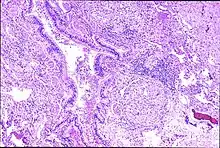

![]() | |

| Peribronchal non-necrotizing granuloma from berylliosis | |

Granulomas are seen in other chronic diseases, such as tuberculosis and sarcoidosis, and it can occasionally be hard to distinguish berylliosis from these disorders. However, granulomas of chronic beryllium disease will typically be non-caseating, i.e. not characterized by necrosis and therefore not exhibiting a cheese-like appearance grossly.[5]